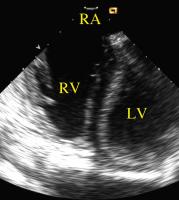

Figure 8: The right ventricle viewed with the AcuNav (TM)-catheter pressed against the roof of the right atrium. LV = left ventricle; RA = right atrium; RV = right ventricle

Keywords: AtriumAtriumCatheterechocardiographyEchokardiographieKatheterventricleVentrikel